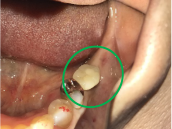

Before

冠の中で大きな虫歯になり支台の役割を果たしていませんでした。

【インプラント埋入前】

冠はブリッジを切断しただけで取れてきました。軟化象牙質を取り除いたところ、歯根しか残っていない状況で保存できるかどうかのぎりぎりのところでした。